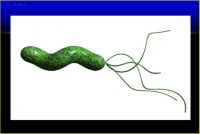

1.幽门螺杆菌英文为H.pyloris简称HP,1983年澳大利亚科学家Warren(罗宾沃伦)和Mashull(巴里马歇尔)发现,于2005年获诺贝尔医学奖;它是一种革蓝染色阴性的螺旋状、*微需氧菌。广泛存在于人类尤其是亚洲人的胃液中,是许多慢性胃病发生、发展中的一个重要致病因子。HP的感染率在我国高达50%;

幽门螺杆菌与胃炎的关系非常密切。活组织病理学检查时可同时检测幽门螺杆菌,并可在内镜检查时再多取1块活组织做快速尿素酶检查以增加诊断的可靠性。

1.根除幽门螺杆菌成功根除幽门螺杆菌可以预防消化性溃疡及降低胃癌的发生率,可以缓解部分患者消化不良症状。2006年中国慢性胃炎共识意见,建议根除幽门螺杆菌特别适用于:伴有胃粘膜糜烂、萎缩、肠化生、异型增生;有消化不良症状;有胃癌家族史。治疗方案:常用的有铋剂加两种抗生素或质子泵抑制剂加两种抗生素组成的三联疗法;